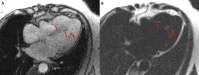

The Society for Cardiovascular Magnetic Resonance (SCMR) is an international society focused on the research, education, and clinical application of cardiovascular magnetic resonance (CMR). Case of the week is a case series hosted on the SCMR website ( https://www.scmr.org ) that demonstrates the utility and importance of CMR in the clinical diagnosis and management of cardiovascular disease. Each case consists of the clinical presentation and a discussion of the condition and the role of CMR in diagnosis and guiding clinical management. The cases are all instructive and helpful in the approach to patient management. We present a digital archive of the 2020 Case of the Week series of 11 cases as a means of further enhancing the education of those interested in CMR and as a means of more readily identifying these cases using a PubMed or similar search engine.